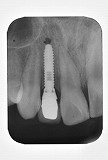

歯列矯正 歯肉形態修正手術 インプラント メタルボンドを併用した症例です。

この治療では1本の歯も削ったり、抜いたりはしていません。

- 先天的に上顎側歯列が欠如している患者さんです。

- はじめに矯正治療を行い、本来歯があるべき位置に矯正して、インプラント手術のためのスペースを確保しました。

- 矯正治療終了後に歯肉の形態修正手術を行いました。

- 本来の側切歯部分にインプラント埋入

- メタルボンドにて修復